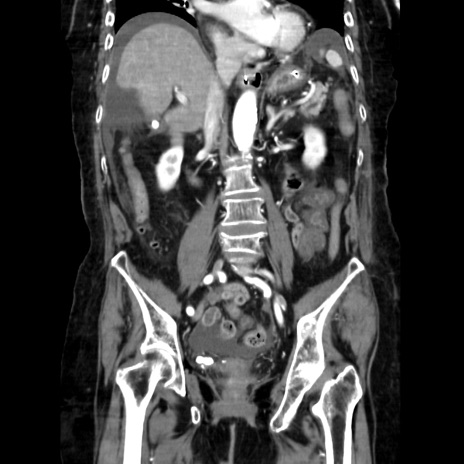

症例40(冠状断像)

【症例】90歳代女性

【主訴】腹痛・嘔吐

【現病歴】 食欲低下、嘔吐があり昨日他院受診。肺炎と診断され入院となる。入院後より腹部全体に圧痛あり。胃管留置され経過みていたが、症状持続するため、

当院転院となる。

【既往歴】胸椎圧迫骨折、胆石症

【身体所見】腹部:中央に激痛あり、圧痛あり、反跳痛不明

【データ】WBC 17100、CRP 18.82

冠状断像